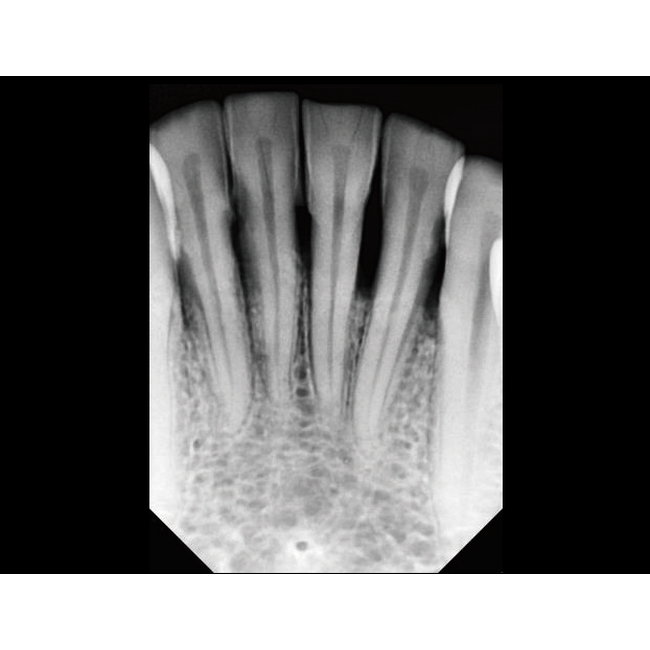

Интеллектуальная система позиционирования делает работу с EzRay Air Wall невероятно простой, а уменьшенный размер фокального пятна обеспечивает снимки высочайшего качества.

Вне зависимости от используемого датчика, EzRay Air Wall гарантирует превосходный результат благодаря фокальному пятну 0.4 мм.